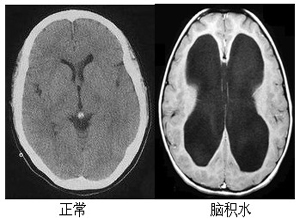

腦積水是腦脊液生成過多或循環(huán)吸收障礙,而致腦脊液在腦室系統(tǒng)或蛛網(wǎng)膜下腔內(nèi)瘀積,并不斷增長,壓力增高,腦室擴大,即為腦積水,是神經(jīng)系統(tǒng)疾病的一種,對嬰兒危害很大,那么嬰兒腦積水有哪些癥狀呢?

當然,腦積水的診斷一定是要通過超聲、核磁或者CT等影像學診斷才能確診,或者通過顱腦x線片檢查,或者是頭顱二維超聲檢查等方法確診,然后進行手術治療。一旦確診為腦積水,就需要在腦外科或者小兒神經(jīng)外科醫(yī)生的診斷下進行合理治療。這種病越早治療治愈率越高,同時也需要使用藥物同步治療。家長也應該注意做好日常的各項護理工作,多注意觀察患者的體溫變化,這樣對于病情的恢復會有更大的幫助。